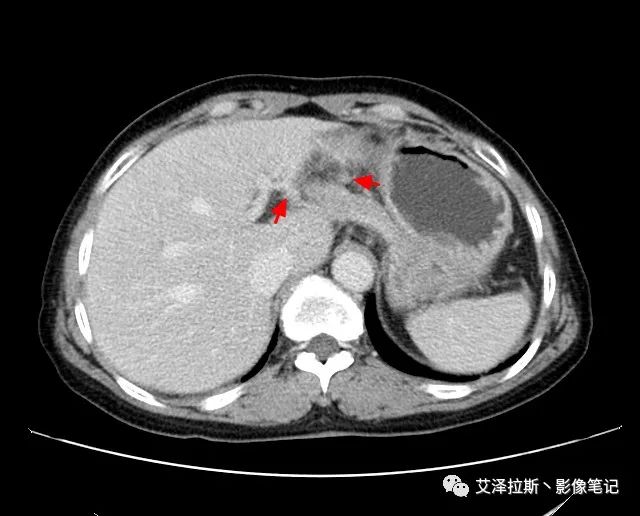

【影像所見】 胃竇部狹窄,胃壁環形增厚,小彎側見一巨大潰瘍,周圍伴“環堤征”,漿膜面不完整,胃周脂肪見網格狀條索影,病灶與肝臟左葉、胰腺鉤突脂肪間隙消失,增強掃描病灶明顯強化。引流區內約15個區域淋巴結受累。

【診斷意見】 胃竇部胃癌(T4N3期) 該病例腫塊突破漿膜層,與肝臟左葉、胰腺鉤突分界不清,脂肪界面消失,定為T4期; 受累及的淋巴結為15個區域,定為N3; 有無遠處轉移尚不明確,所以M期暫時無法確定。